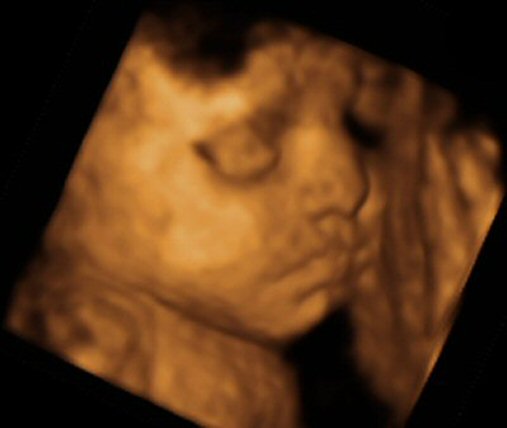

- 29 week 4D scan

- The scan photos shown below are 3D images from the babybond 4D scan at 29 weeks gestation.